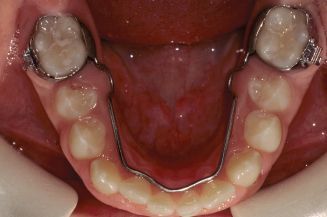

Other types of orthodontic appliances may also be used during the course of treatment. Some of these appliances are removable and can be taken in and out of the mouth, while others will be attached to the teeth until they are no longer needed.

- Maintaining the space for a permanent tooth when a baby tooth has been prematurely lost

- Minor tooth movement